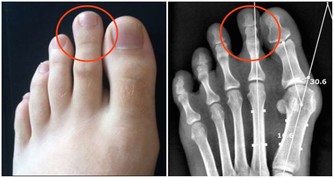

第二,每年一次針對性的體檢,主要是糖尿病及其並發症,包括眼底和足部,平時如有不適,及時就醫。

第三,注重足部的保健。糖友們每天自我檢查雙足,避免過度行走和勞累,選擇舒適的鞋襪。注意足部的清潔衛生和護理,洗腳的水溫不要超過40攝氏度,避免燙傷。